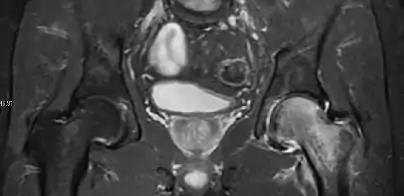

Magnetic resonance imaging

Many pathological conditions of the hip are detected early by MRI due to its high soft tissue resolution and sensitivity. Its accuracy in studying acute hip pain in children has proved to be superior to ultrasound and plan film radiography. However, MRI accessibility and the need of sedation relegate its use to selected cases in which diagnosis is not clear with less demanding techniques. These include differentiating transient synovitis from a septic arthritis or osteomyelitis, diagnosis of inflammatory joint disease or bone tumors, and early detection and follow-up of Perthes disease.[1]

In adults, MRI is currently playing a definite role in the assessment of osteoarthritis. Although traditionally belonging to the arena of radiographs, the role of MRI has been stressed after the term femoral acetabular impingement was coined in 2003. Growing interest has been focused in accurate diagnosis of the acetabular and femoral morphological abnormalities that may lead to early osteoarthritis.[1]

MR imaging is considered paramount to these objectives, mainly when surgery is considered, due to the ability of MRI to portray the whole section of the femoral neck surface, as well as to image the labrum and articular cartilage.[1]

Most of the angles and measurements described in the plain radiograph section can be accurately reproduced on MRI. In addition, the superiority of MRI resolution with intra-articular contrast allows detection of labral and chondral abnormalities that may influence the choice of medical, percutaneous, or surgical management (Figure 9).[1]

Figure 9:

Sagittal T1 weighted image showing anterosuperior labral tear.[1]

Sagittal T1 weighted image showing chondral lesion.[1]

Sagittal CT-arthrography showing posteroinferior chondral injury.[1]

Coronal CT-arthrography (d) showing ligamentum teres tear.[1]